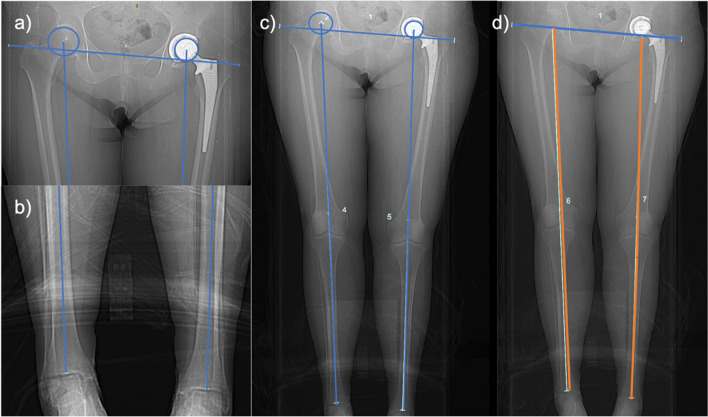

Objective: To compare the magnitude of post-arthroplasty leg length discrepancy (LLD) and incidence of clinically significant LLD measured on CT scanogram using a commonly used measurement method (from the acetabular apex to tibial plafond) to an alternative technique avoiding the use of the acetabular prosthesis as a landmark and to assess inter-observer and intra-rater reliability of the new technique.

Materials and methods: In this retrospective study, post-arthroplasty LLD measurements were conducted in 100 hips by two interpreters on CT scanogram scout views from the acetabular apex to the tibial plafond (AA-TP) and the inter-teardrop line to the tibial plafond (IT-TP). Aggregate means and proportions of clinically relevant LLD (≥ 10 mm) were compared between methods. Inter-rater reliability was calculated, and both interpreters repeated measurements on ten randomly selected patients to calculate intra-rater reliability.

Results: The commonly used AA-TP technique overestimated LLD by 3.7 mm compared to the IT-TP technique. The odds of LLD measurement exceeding the clinically significant threshold of 10 mm were 3.8 times higher when using the AA-TP technique. Excellent inter-rater (ICC 0.984, 0.958) and intra-rater reliability (ICC > 0.9) were found for both techniques.

Conclusion: CT scanogram measurements from the acetabular apex to the tibial plafond often overestimate operative limb length due to reference landmarks in different axial planes. Measurements from the inter-teardrop line to the tibial plafond yield significantly lower LLD values, possibly reflecting actual limb length better. The authors recommend using the inter-teardrop line and tibial plafond as reference landmarks to improve LLD assessment accuracy post-arthroplasty.